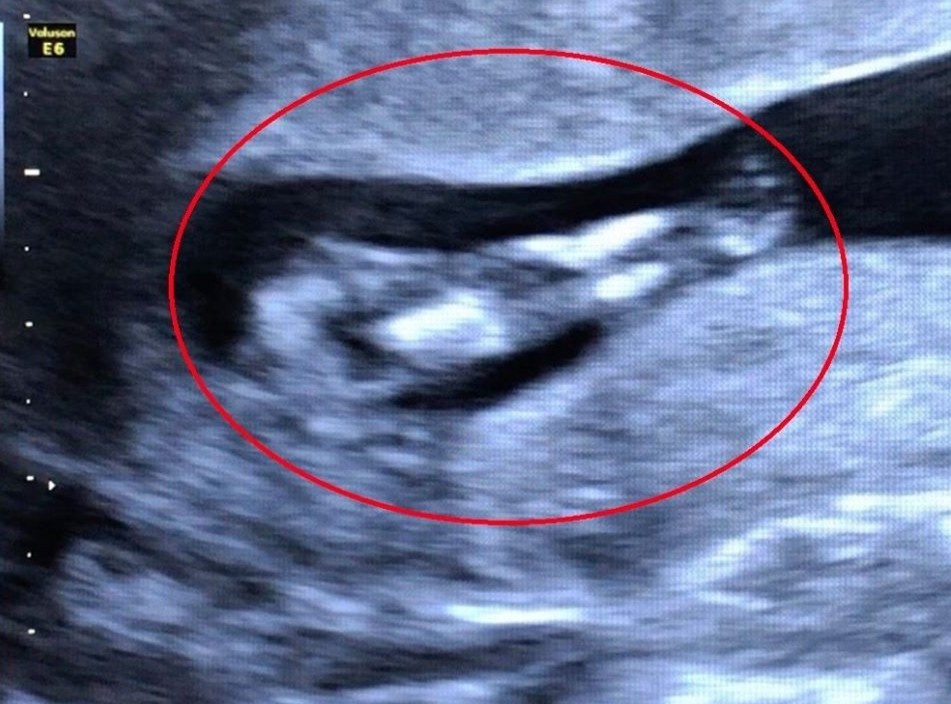

Tình trạng dây rốn quấn quanh cổ thai nhi một hay nhiều vòng do trẻ thường xuyên cử động, xoay chuyển trong không gian tử cung chật hẹp của mẹ.

Trường hợp dây rốn quấn quanh cổ thai nhi không quá hiếm gặp, nhưng quấn đến 4 vòng thì tương đối hy hữu.

Thai nhi nấc cụt không phải là một hiện tượng bất thường, nhưng nó có thể là biểu hiện của việc dây rốn bị chèn ép hoặc sa.

Trước nguy cơ ảnh hưởng đến tính mạng của mẹ và bé vì có bất thường về dây rốn, bác sĩ đã phẫu thuật khẩn cấp để cứu các bệnh nhân.

Qua hình ảnh siêu âm, bác sĩ phát hiện thai nhi có hai chân dính vào nhau giống như đuôi cá, bất thường ở bàng quang và hệ tiết niệu.